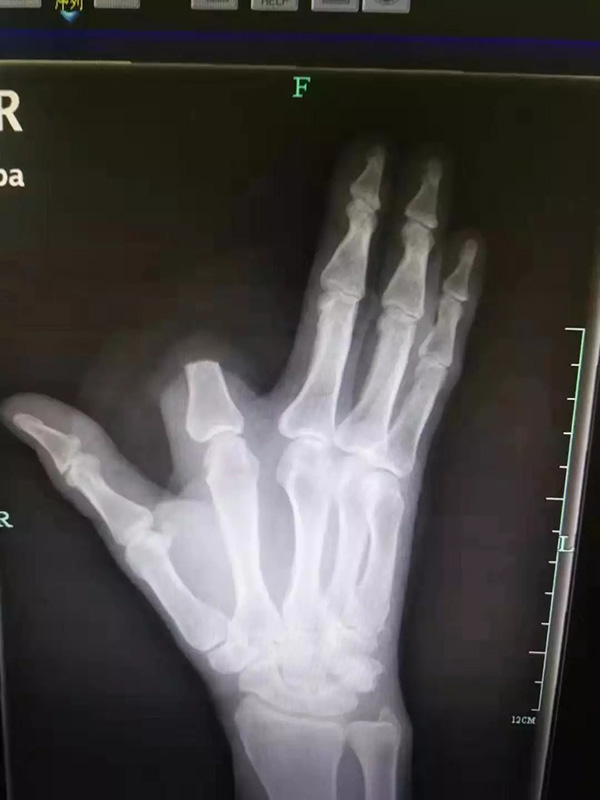

“打开一看,我们发现患者的食指少了一大截。”袁丞达一问,张先生颤抖着回答:“砍了,保命要紧!”

原来,被咬后,张先生仔细一看,发现伤人的是条剧毒五步蛇,怕自己走动后毒性发作,一时恐惧紧张,就拿刀将自己的食指斩断了。事后,他将断指就地丢弃,没有一并带到医院。

检查结果出来,张先生的凝血功能正常,医生为他注射了抗蛇毒血清。本来,断指尚可以再植,如今,只能由骨科医生手术处理断指残端,张先生也将留下终身残疾。